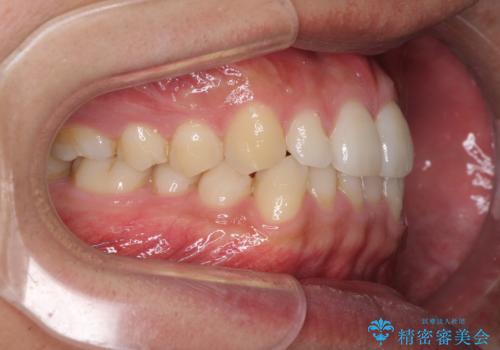

前歯のデコボコとクロスバイト インビザライン矯正治療

- 前歯のデコボコとクロスバイトを治したいとのことで来院された患者様です。

上下顎ともに歯列全体の側方拡大を行い、下顎前歯はIPR(歯と歯の間を削る)によってデコボコとクロスバイトが解消するように設計し、インビザラインにより治療を行うこととしました。

2年弱で終了する予定でしたが、途中来院されなかった時期があり、その後舌側転位している前歯を動かせるところまで動かしたいとのことで4年ほど治療を継続されました。